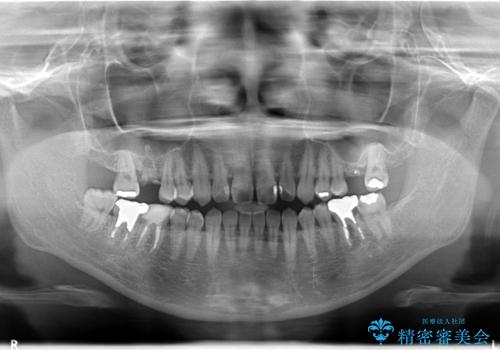

【歯牙移植】親知らずを移植して、インプラントを回避。

- 銀歯の下が大きな虫歯になり、保存困難のためその後の治療計画について悩まれていた患者様です。

患者様と相談し、親知らずを用いて歯牙移植を行いました。

移植歯はアンキローシス(歯と歯槽骨の間の歯根膜がなく、歯の根と骨が結合している状態)するリスクがあります。

アンキローシスを避けるため、術中や術後管理に注意が必要です。